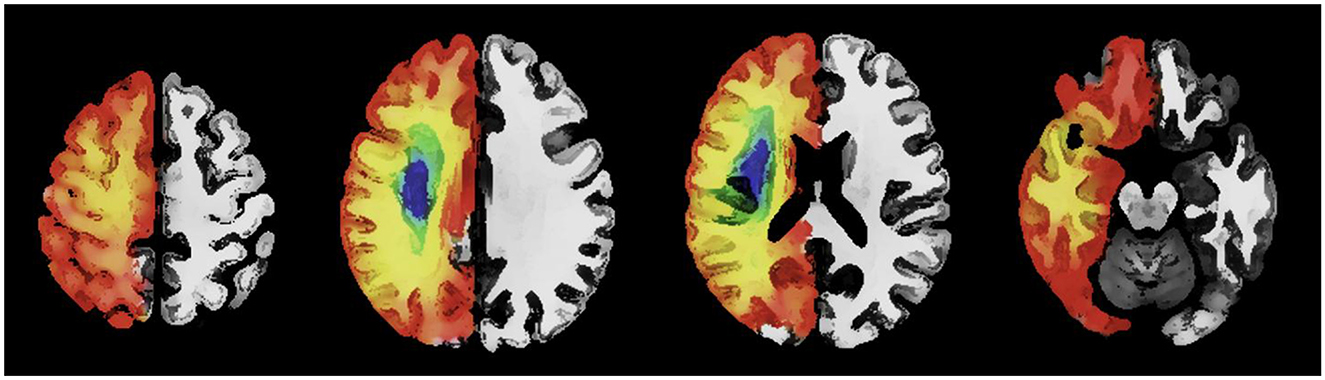

Sanctuary sites are regions of potentially salvageable penumbral tissue predominantly present within the frontal, parietal and occipital cortex (1). Figure 1 is a schematic representation of sanctuary sites (1) created using published digital maps of cortical stroke with documented vessel occlusion (3, 32–34). Segmented infarcts from T2-weighted magnetic resonance images were averaged to generate a probability of infarction at a voxel level for each arterial territory. The probability of infarction at each voxel (Pi) for the combined arterial territories was calculated as previously described (1). The probability of sanctuary sites was calculated using the formula probability of sanctuary sites = 1–Pi. Sanctuary sites were identified as regions with a probability of infarction (Pi) < 0.1 (1).

Figure 1. An axial image with a schematic representation of the topography of sanctuary sites created using published digital maps of cortical stroke with documented vessel occlusion. Leptomeningeal collaterals may support blood flow to the superficial compartment to maintain penumbra. Regions (red/orange) have a low probability of infarction and a high probability of sanctuary sites. Regions (blue/green) have a high probability of infarction and a low probability of sanctuary sites.

Historical data and current works have alluded to the presence of sanctuary sites (1, 3, 13, 17, 33, 35–38). Following proximal MCA occlusion it is well recognized that the highest probability of infarction centers around the striatocapsular region and the centrum semiovale, followed by the insular (24, 33, 35, 37, 39, 40). Compensatory flow from posterior cerebral artery (PCA) and anterior cerebral artery (ACA) to MCA through LMA may enable sparing of cortical regions of the frontal and parietal lobes from infarction (1, 13, 17, 33, 35–38), following reperfusion. Although we acknowledge inter-individual variability in LMA, we propose that knowledge of the detailed anatomy of the anastomoses as described by Vander Eecken and Adams (13), and others (14–16, 26) may be useful to increase our understanding of the potential locations of sanctuary sites (1, 3, 32–34). Table 1 describes the possible locations of sanctuary sites using data from previously published digital atlas of probability of infarction (3, 32–34) and the sanctuary sites map (1). To assist with anatomic interpretation, a database Talairach Daemon was used to relate the voxel coordinate in the X, Y, and Z planes (available at http://www.talairach.org/daemon.html).

The presence of LMA between cortical branches of the ACA and MCA may support blood flow to the superficial compartment to maintain penumbra (see Figure 1). Therefore, the concept of sanctuary sites (1) may provide a framework for identifying patients with a large core (95–98) who have the ability to reach a good functional outcome following treatment with clot retrieval. Imaging studies with MRI suggest that in some cases penumbra can exist up to 48 h (99). Development of adjuvant medical therapies which augment blood flow through LMA (100) may enable extension of current time windows for reperfusion therapies and allow successful treatment of patients who require long distance transfer to a comprehensive stroke center for thrombectomy (101). Pharmacological augmentation of blood flow through established LMA may also be sufficient to improve clinical outcome in cases of large and medium vessel occlusion not suitable for endovascular clot retrieval (100, 102–105) or where thrombolysis is contraindicated (100).